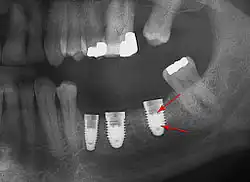

Panorex radiograph showing implants

Xray of four Straumann implants and abutments